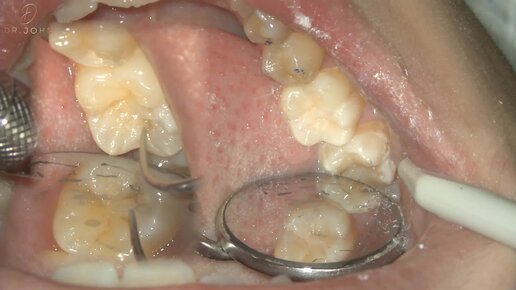

Лечение кариеса нижнего моляра методом окклюзионного композитного ключа